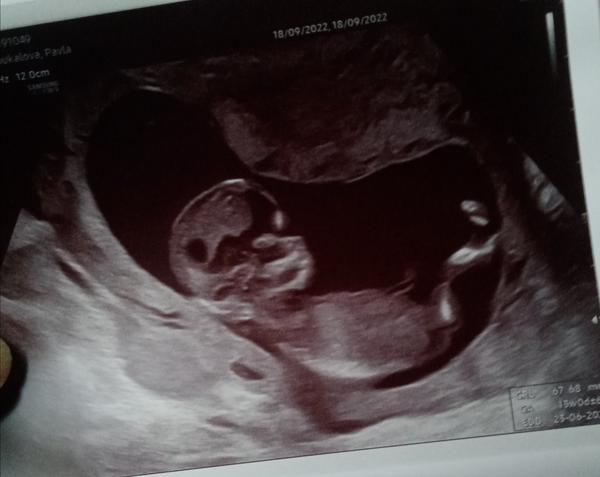

poznáte pohlaví z fotky?

Foto ze screeningu 13+0.

Lékaře jsem se neptala, pohlaví nevíme, jen mě tak napadlo se zeptat.

A dle čeho se pozná konkrétně třeba tady na té fotce? Jestli teda poznat vůbec jde.

z této fotky pohlaví posoudit nelze. Daná oblast není zachycena.